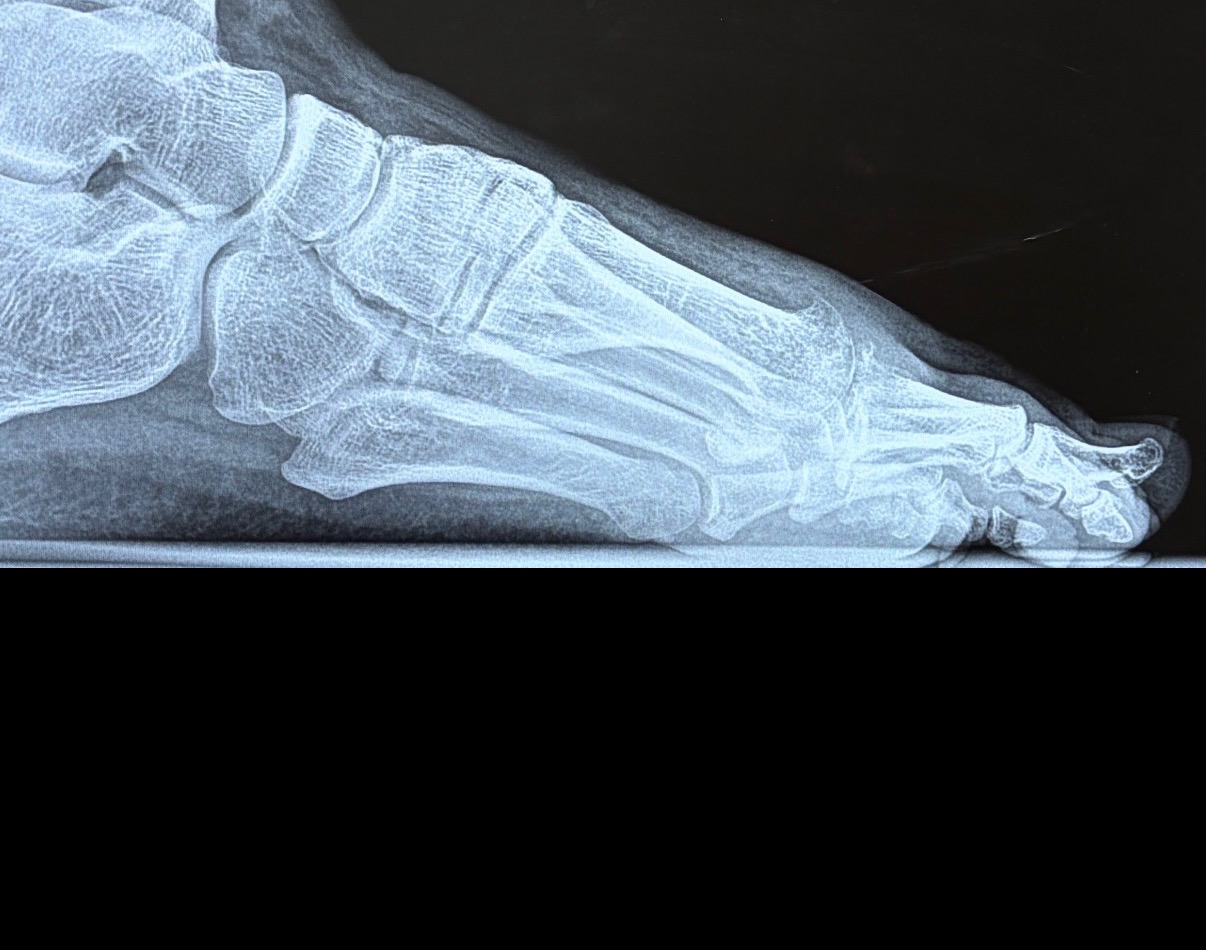

Lateral View

Based on the radiographic images provided, this appears to be a case of hallux rigidus (degenerative arthritis of the first metatarsophalangeal joint).

1. Joint Space Narrowing - Significant narrowing of the first MTP (metatarsophalangeal) joint space - Indicates cartilage loss and degenerative changes - Most prominent at the dorsal (top) aspect of the joint

2. Osteophyte Formation - Visible bone spurs (osteophytes) at the joint margins - Particularly prominent on the dorsal aspect of the first metatarsal head - Classic sign of osteoarthritis in this location

3. Subchondral Sclerosis - Increased bone density (sclerosis) adjacent to the joint surface - Indicates chronic stress and remodeling - Visible as brighter/whiter bone on the x-ray

4. Joint Alignment - Overall alignment appears maintained - No significant hallux valgus (bunion) deformity - Sesamoid bones appear intact

Based on radiographic findings, this appears to be Grade 2-3 hallux rigidus: - Grade 1: Mild osteophytes, minimal joint space narrowing - Grade 2: Moderate osteophytes, joint space narrowing, subchondral sclerosis - Grade 3: Severe osteophytes, marked joint space narrowing, cyst formation - Grade 4: Complete joint destruction